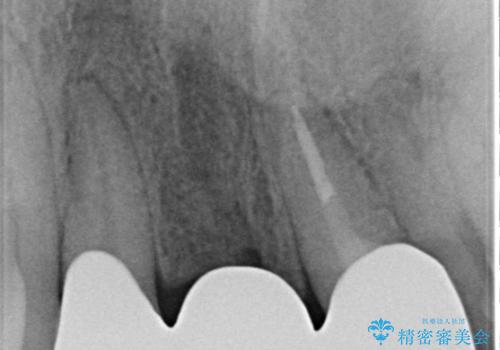

【オールセラミックスタンダード】前歯のブリッジ

- 矯正治療終了後の患者様です。

前歯が欠損しており、ブリッジでの修復を希望されましたので、オールセラミッククラウン(スタンダード)で治療を行いました。